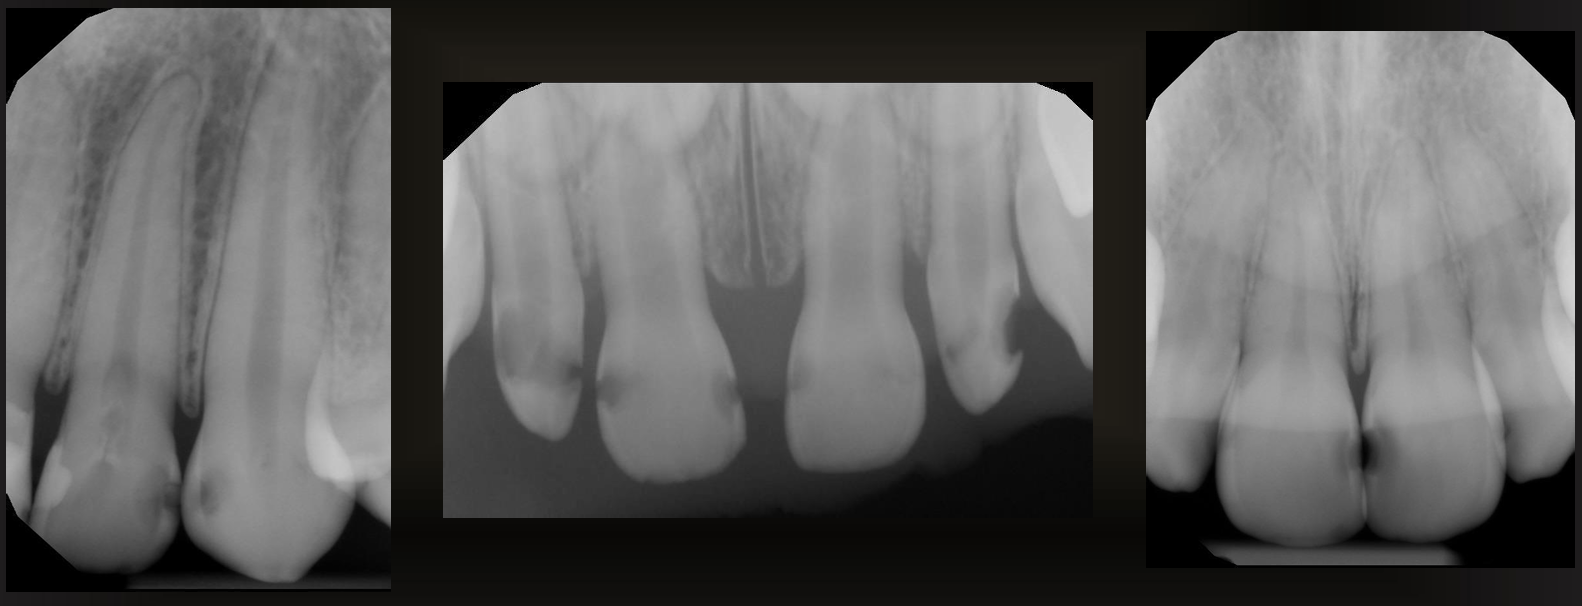

what are the arrows pointing to?

root surface caries

what are the green arrows pointing at?

cervical burnout

how can you tell if its cervical burnout or caries?

there is no bone loss, it affects multiple teeth, and if the angle of the radiograph changes the radiolucency is gone